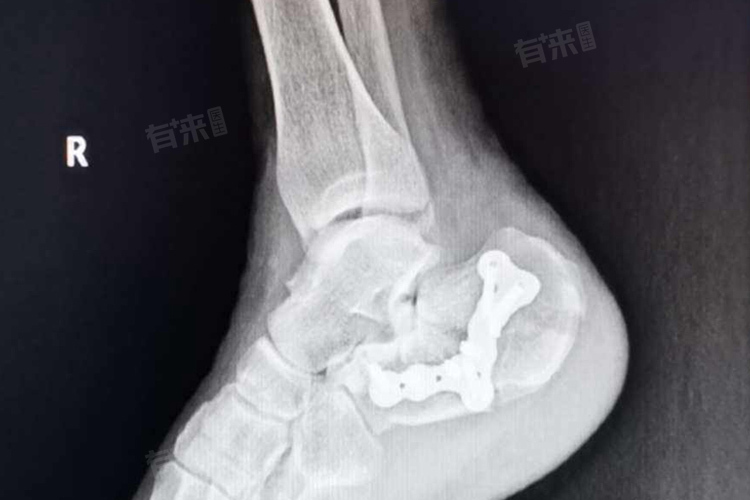

- 手术治疗:如内固定、外固定等。手术治疗通常适用于重度粉碎性骨折,或者保守治疗无效的情况。手术治疗可以更有效地固定骨折部位,促进骨折愈合。然而,手术后的恢复时间也取决于手术的成功程度和术后的康复措施。一般来说,手术治疗后的恢复时间可能在3-9个月之间,但具体时间还需根据患者的具体情况而定。

- 对于多数脚粉碎性骨折,特别是涉及关节面的骨折,通常需要手术治疗,如切开复位内固定术,以恢复骨折的正常解剖结构,术后或康复期间,如感到疼痛,应及时向医生反映,使用合适的止痛药物,确保疼痛得到有效控制。